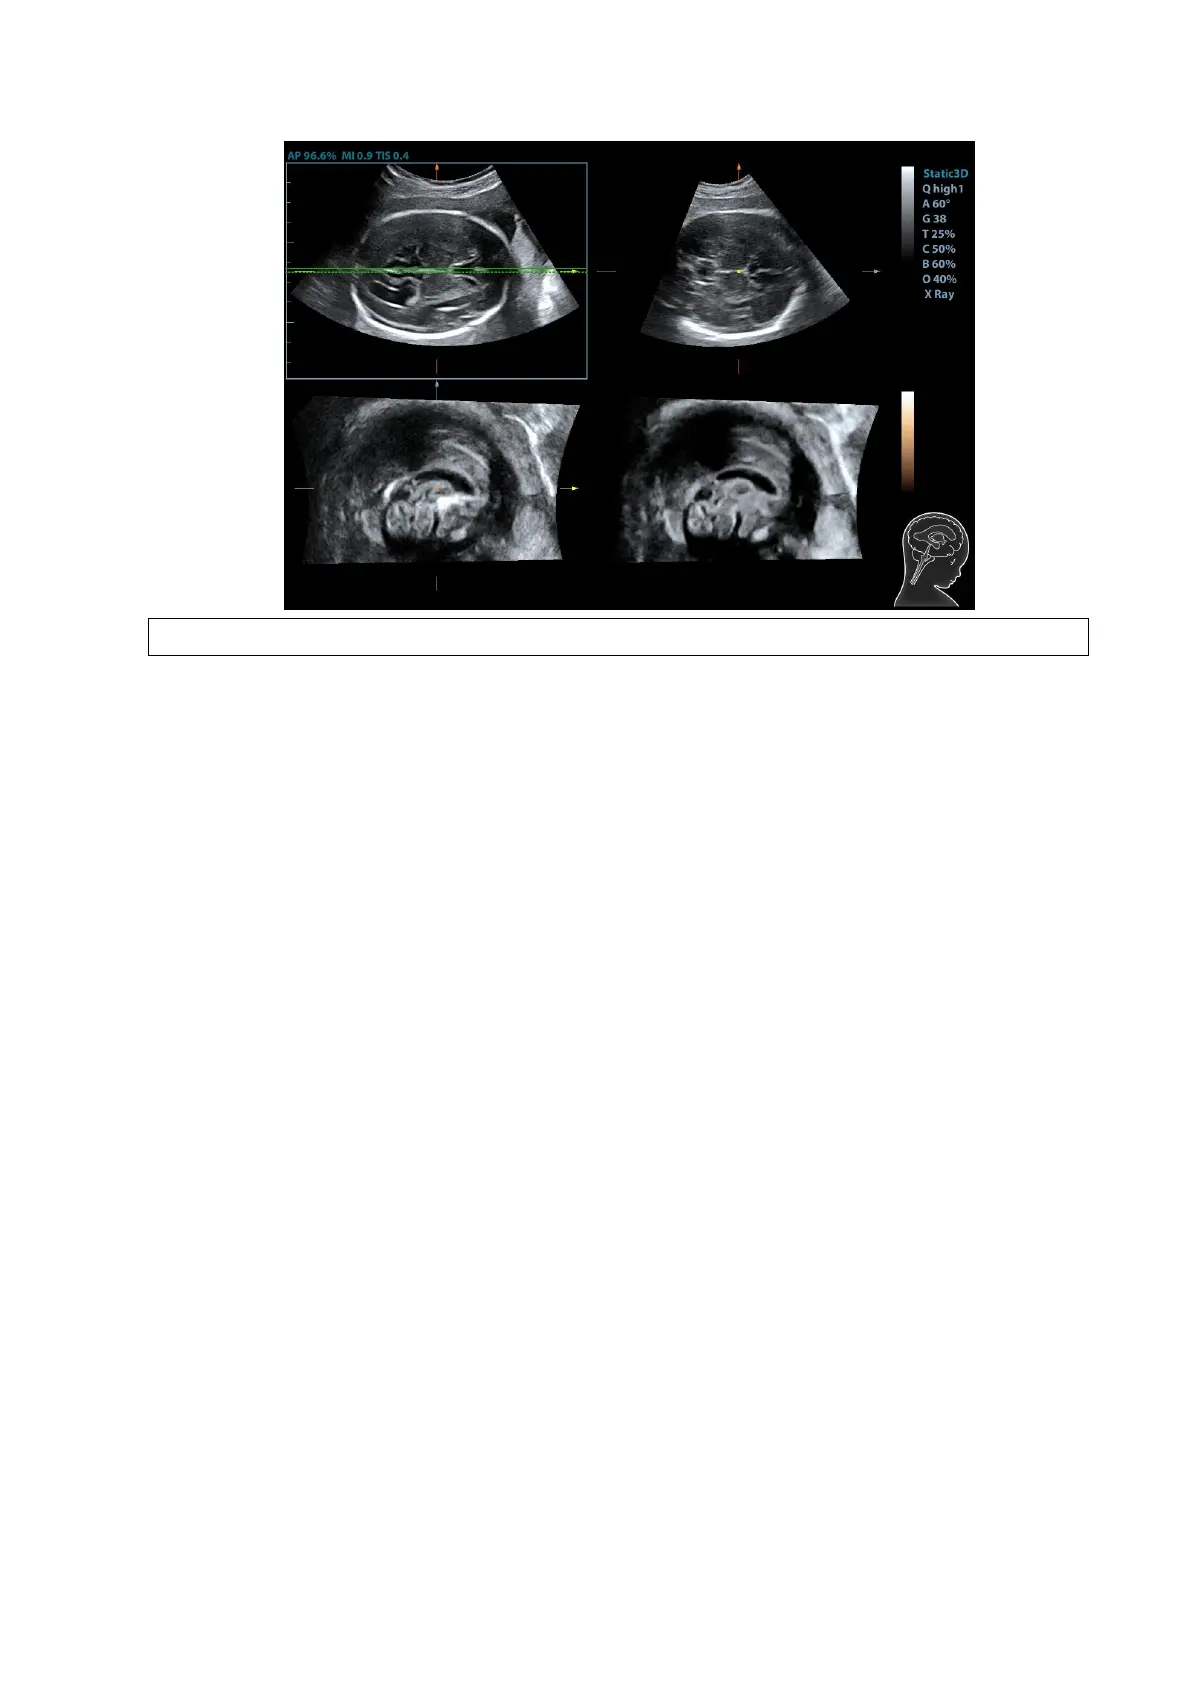

5. Tap [OK] to accept the edit to the MSP. The system recalculates the TCP, TTP and TVP

according to MSP’s position. The position and the angle for TCP, TTP and TVP appears on

MSP plane.

6. Tap [TCP]/[TTP]/[TVP] to select the plane, and rotate <M>, <PW> or <C> knob to rotate the

image plane along with X/Y/Z axis. The angle value appears on the right of the image.